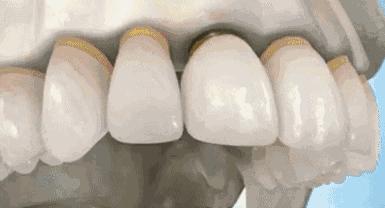

这个时候就要及时的给牙齿由内而外的保护起来,内部桩核修复,让牙齿内部坚固。外部冠修复,让牙齿受力均匀,减少碎裂风险。